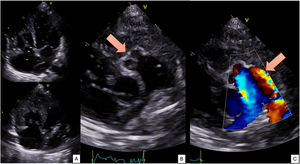

- Between atrial fibrillation and ablation: an unexpected finding

- Ismael Arco Adamuz, Torcuato Garrido-Arroquia Jurado, Rocío García Orta

- Rev Esp Cardiol. 2025;78:1018-9